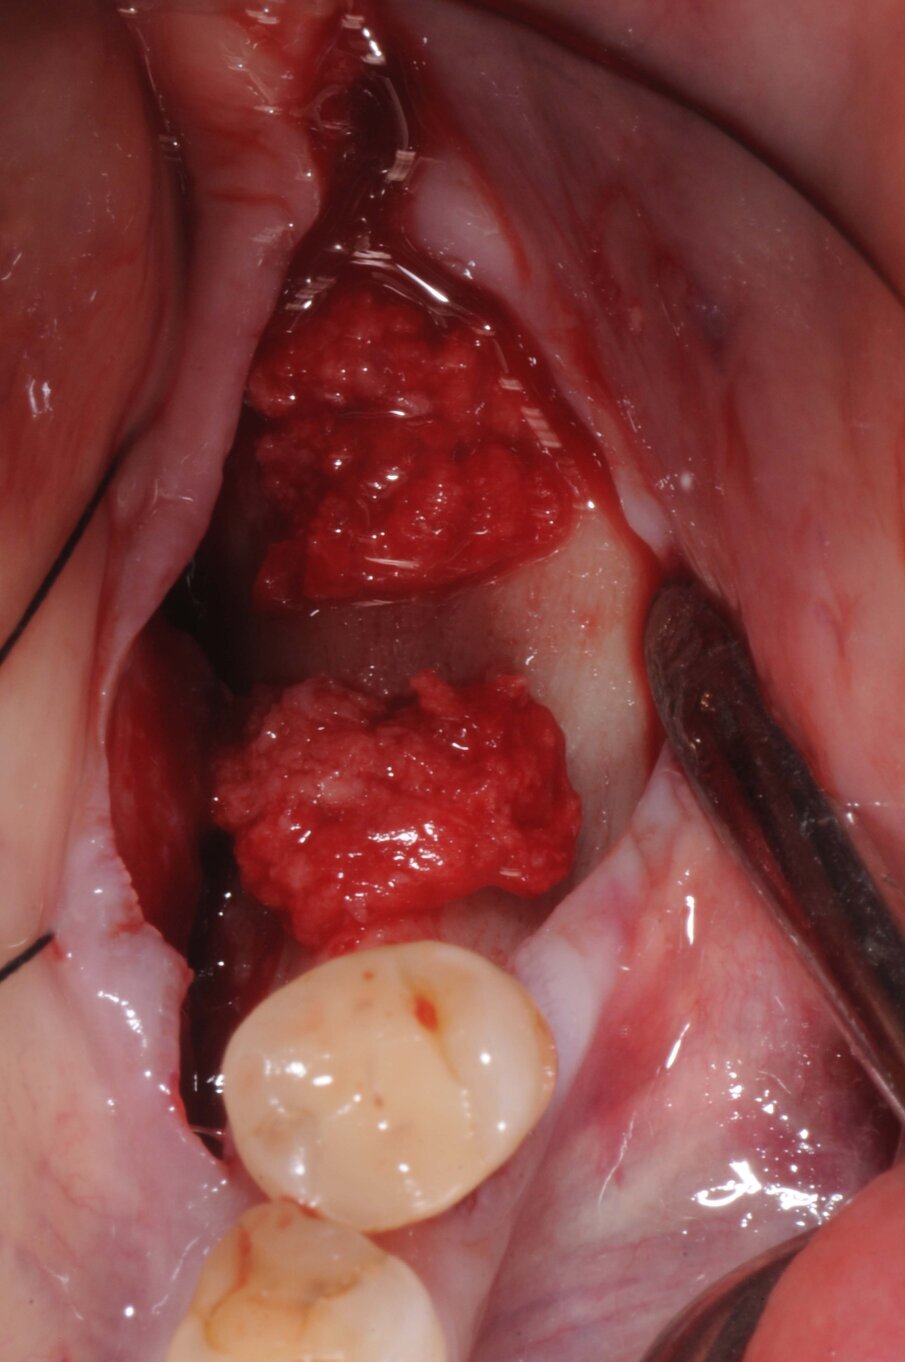

Il giorno della chirurgia fu somministrata una terapia antibiotica profilattica, per mezzo di amoxicillina più acido clavulanico, della durata di sei giorni. Dopo somministrazione di anestesia locale con Articaina al 2% 1:100000, fu eseguita un’incisione crestale estesa nel solco del dente 35 senza incisioni di rilascio. Furono eseguite le osteotomie a bassi numeri di giri senza irrigazione come da protocollo BTI e furono inseriti due impianti BTI CORE 4,5X3,75. Al di sopra degli impianti fu collocato osso di recupero dalla fresatura mischiato con PRGF e il tutto fu protetto da due membrane di fibrina ottenute per centrifugazione del sangue della paziente con tecnica Endoret PRGF. Furono applicate suture a punti staccati con filo Supramid Braun 5.0 (Figg. 5-7).